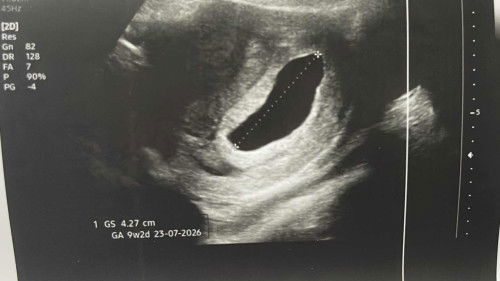

tadi baru selesai repeat scan dan doktor di klinik pertama cakap kantung kosong & perlu dnc. sudah buat surat refer ke hospital. suspect missed miscarriage. saya terus ajak husband pergi ke klinik kedua untuk second opinion sebab doktor pertama taknak buat tvs scan sebab dia cakap memang kosong & rugi kalau buat. bila scan di klinik yang kedua, melalui tvs scan, doktor cakap janin ada ( tapi mungkin tersilap tengok sebab janin terlalu kecil), yolk sac ada, no heartbeat saja sebab masih kecil memandangkan haid saya sangat tak teratur. apa pendapat mommies? perlukah saya ke hospital untuk pemeriksaan susulan atau tunggu lagi 2 minggu based on doktor kedua? sekarang no bleeding atau sakit di bahagian rahim or perut. #Needadvice #askmommies #sharing #firstmom